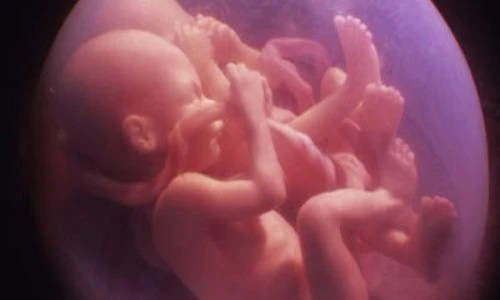

Với những trường hợp sinh ba trở nên, mổ đẻ thường là bắt buộc vì hiếm khi nào cả ba bé đều có thể quay đầu trong bụng mẹ một cách hoàn hảo được.

Thậm chí, các bé còn đạp nhau giành chỗ trong không gian chật hẹp.

Mặc dù vậy, ai cũng phải công nhận rằng các cặp sinh đôi khi ra đời đều trông rất đáng yêu.